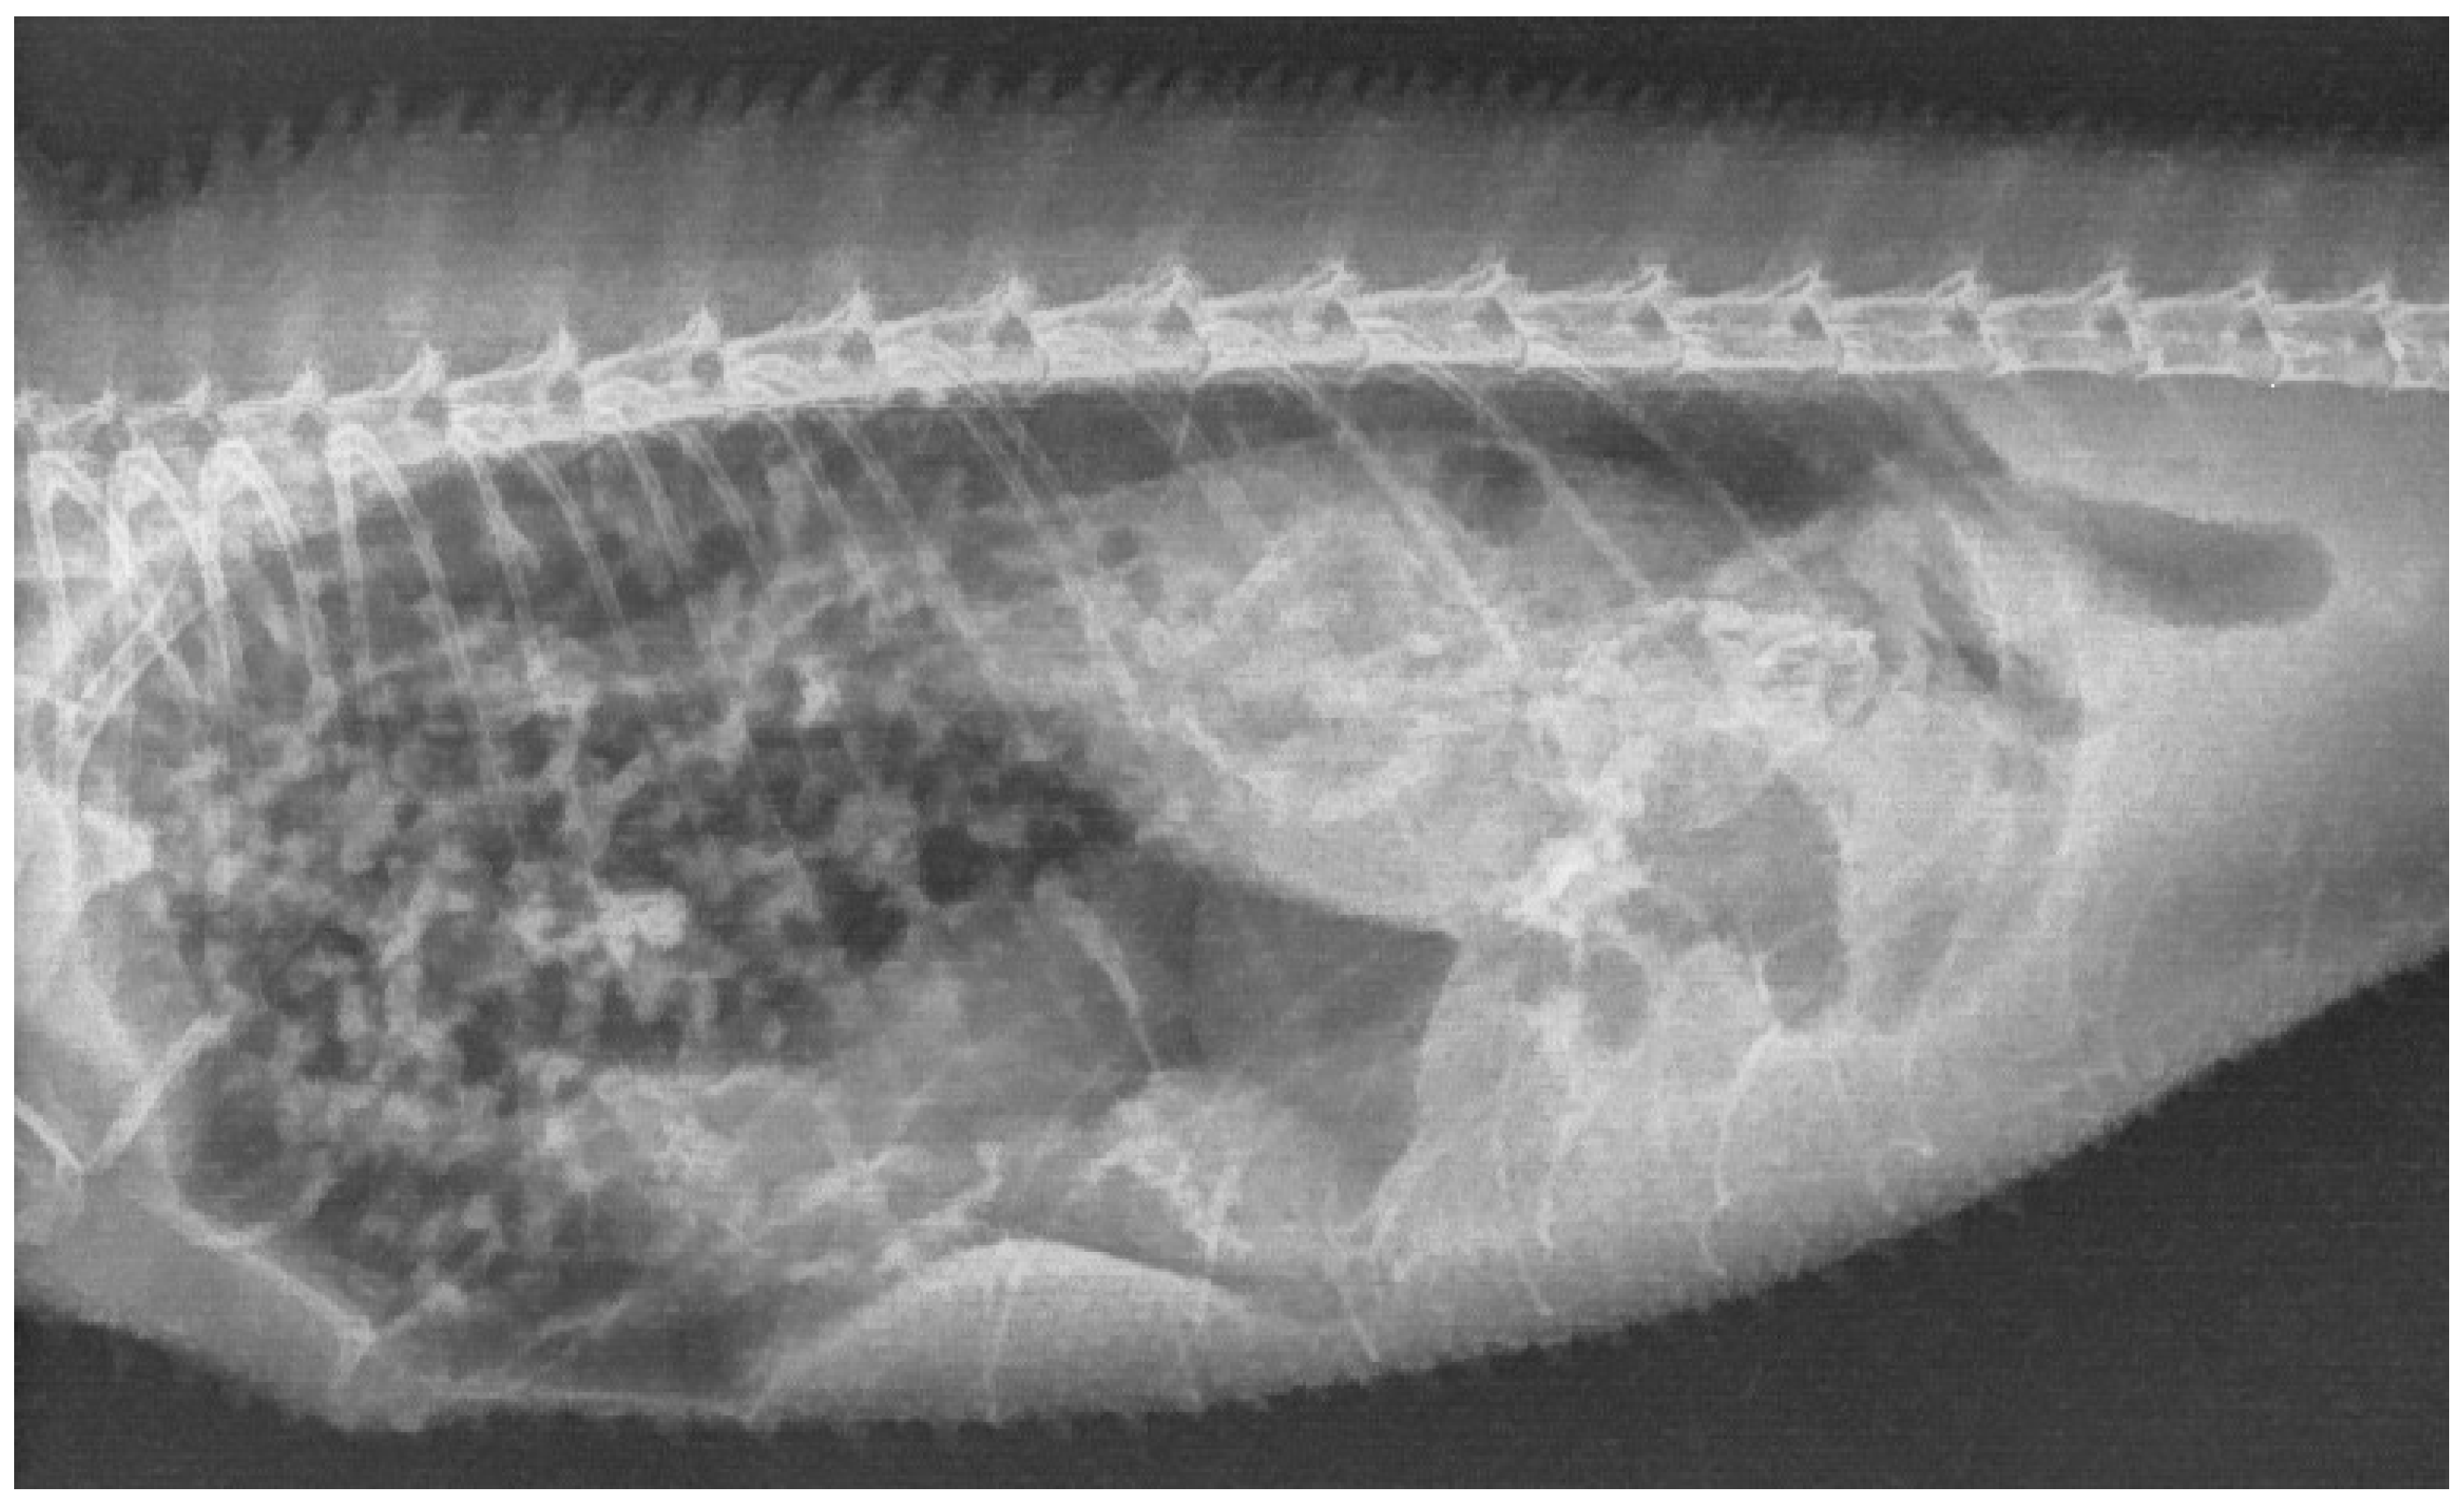

2. Case Description